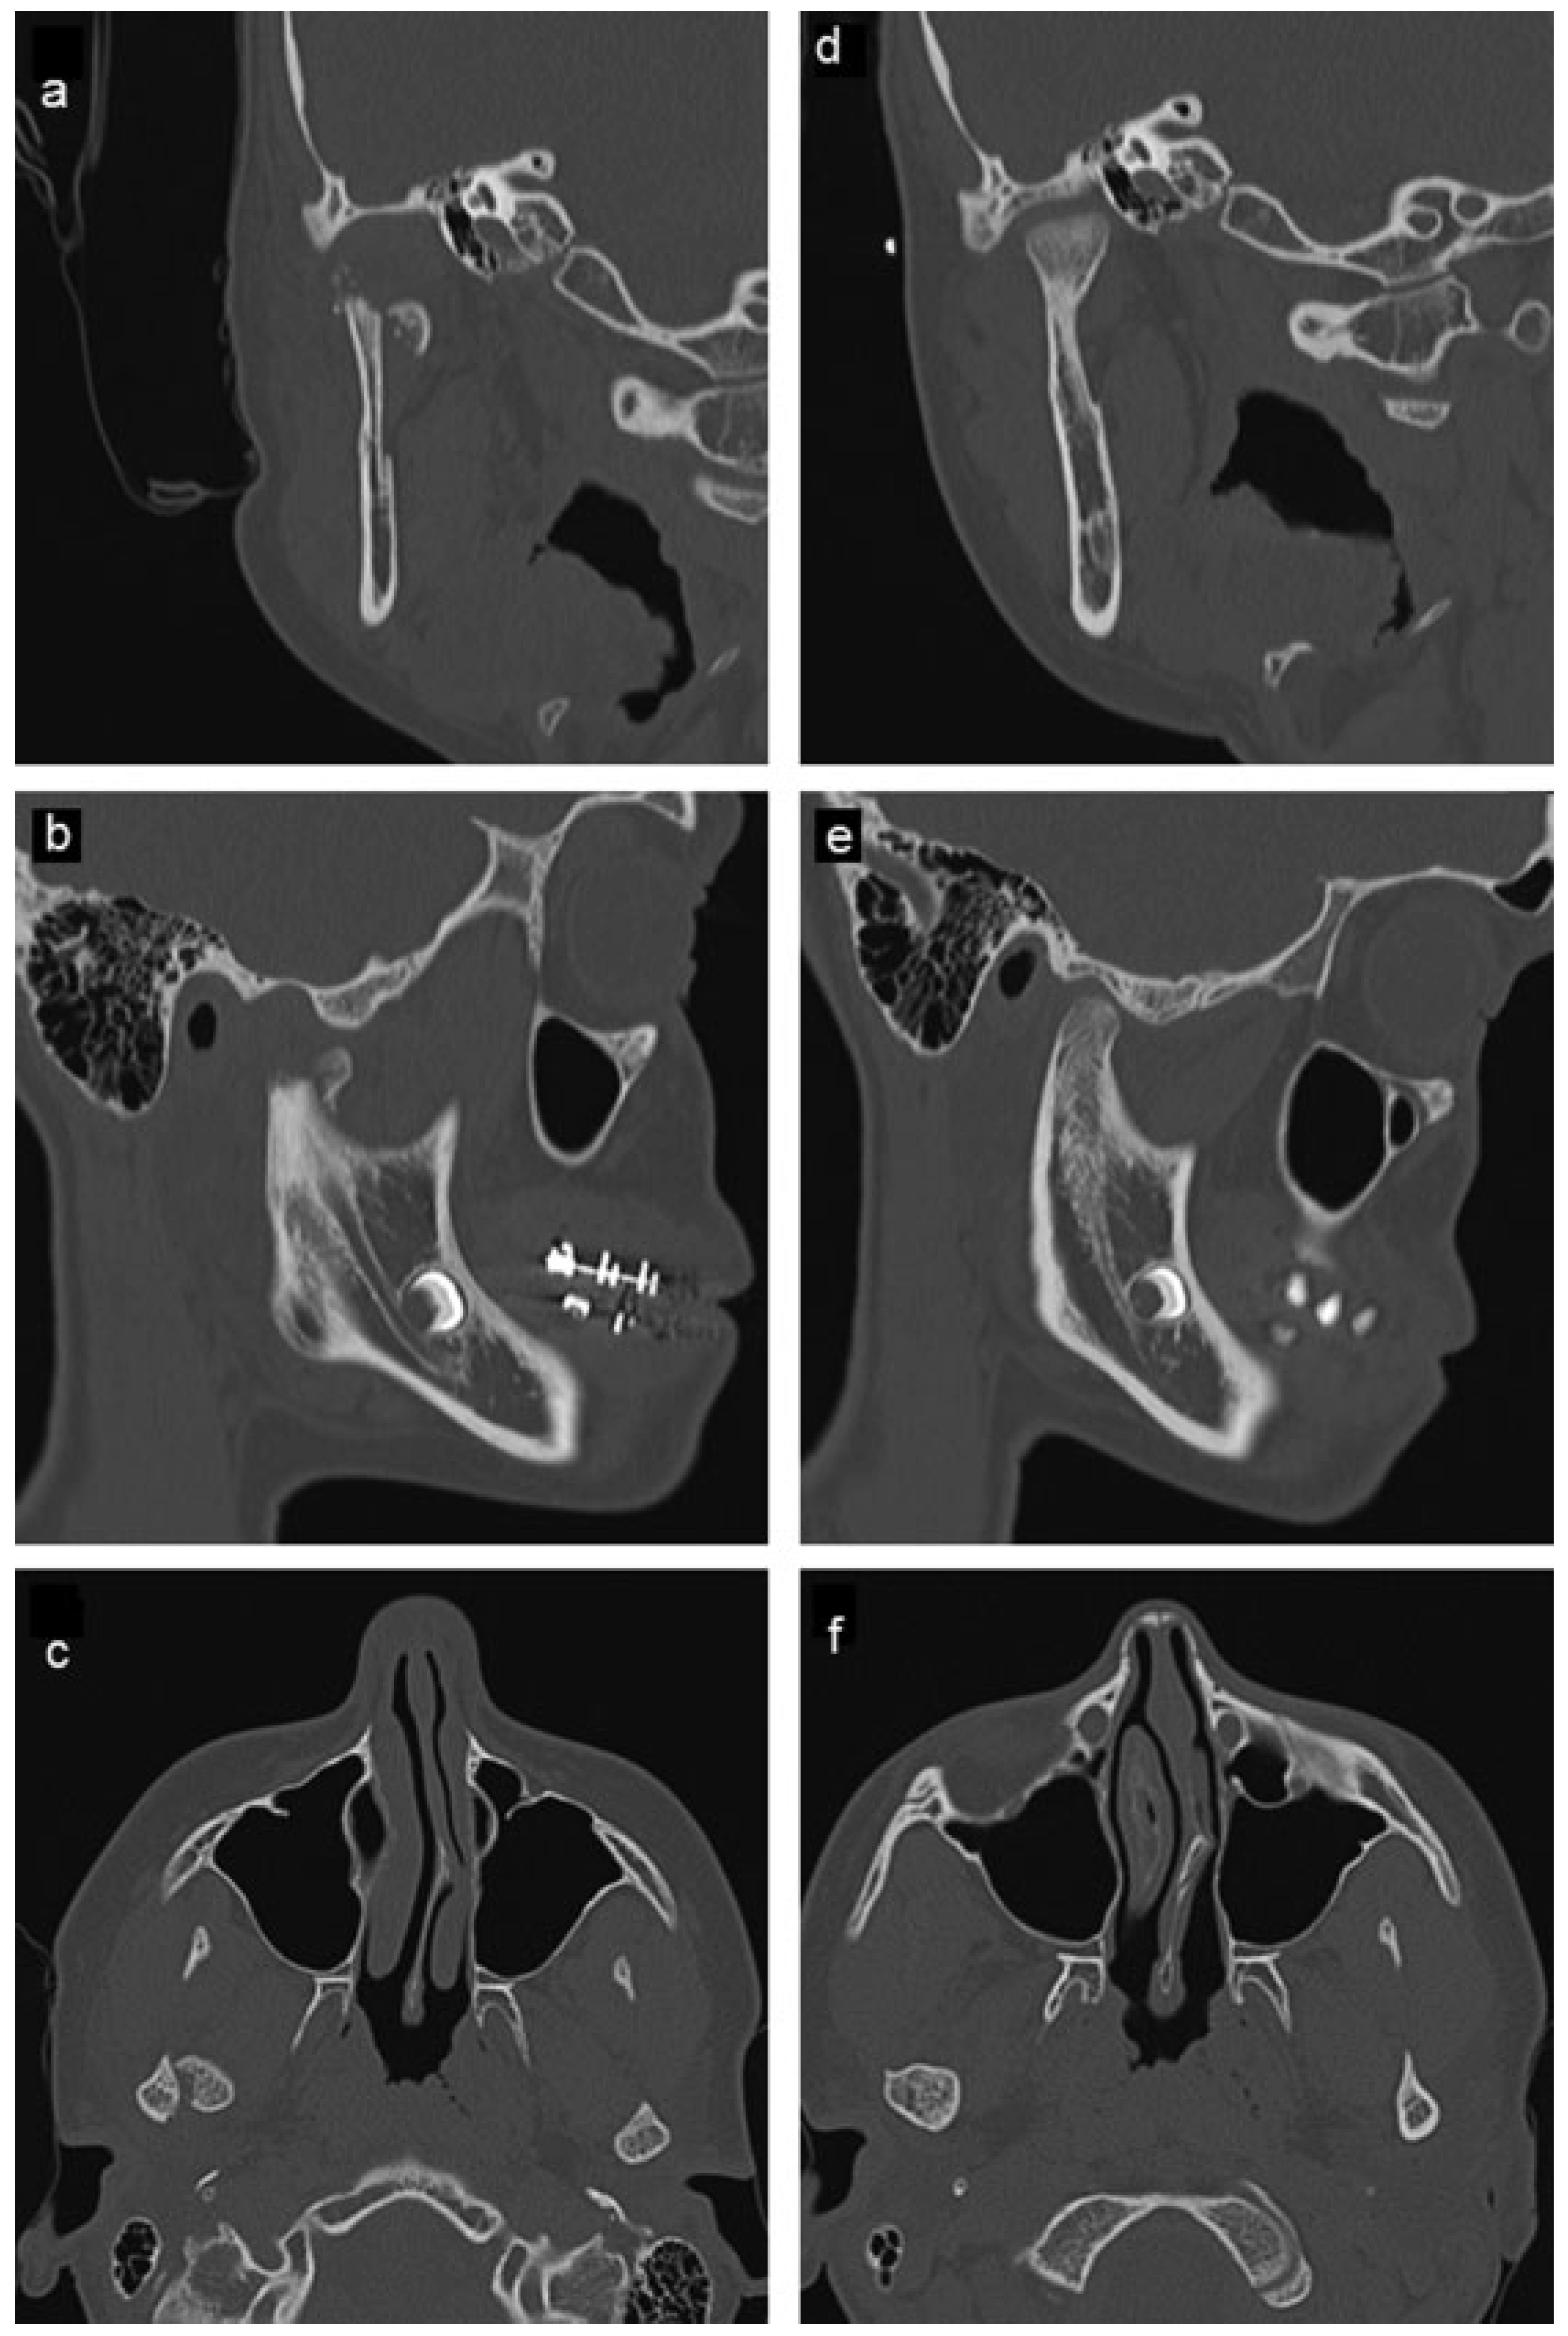

The second patient, a healthy 21-year-old male patient presented to the emergency department at another health institution after being involved in interpersonal violence and falling on his chin. He suffered a right-sided displaced and left-sided nondisplaced condylar neck fractures and a displaced mandibular symphysis fracture. A CT scan was taken (Figure 3a–c and Figure 4a–c). The patient underwent open reduction and internal fixation of the symphysis fracture; and nonsurgical treatment of the bilateral condylar fractures with placement of Erich arch bars and intermaxillary elastics with light function.

The patient was first seen at our clinic for a follow-up evaluation 6 months after the initial treatment. At this time he had regained full mandibular function and denied myofascial or TMJ symptoms. He also denied limitation of motion, noise with TMJ function, and was tolerating a normal diet. His occlusion was a stable class I with good interdigitation. There was an excellent range of motion with slight deviation to the right with wide opening. There was no myofascial pain or joint pain with occlusal loading. A CT scan was obtained due to concerns by his previous physician regarding the possible need to surgically reposition the previously displaced condyle d–f and Figure 4d–f). This CT scan showed reformation and repositioning of the right condyle with normal cortical and cancellous anatomy but with a slight anteroinferiorly displaced position with associated mild flattening of the condylar head. Additional treatment was not advised.

Figure 3. (ac) Comparison between pretreatment and (df) 6-month posttreatment computed tomography of patient 2. Right-sided, medially, and inferiorly displaced condylar neck fracture is shown in pretreatment images as well as posttreatment remodeling in a slightly anteroinferiorly displaced position and flattening of the condylar head. Remodeling of the glenoid fossa via downward growth is again noted, but to a lesser degree than in patient 1.